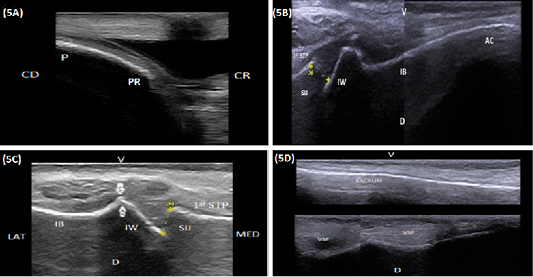

(A) Longitudinal sonogram (10 MHz linear rectal probe, 5 cm depth) of the pubis (P) in a 7-year-old cow showing the pubic rim (PR), caudal direction (CD) and cranial direction (CR). (B) Longitudinal sonogram (10 MHz linear rectal probe, 5 cm depth) in a 6-year-old cow showing the medial aspect of the acetabulum (AC), the medial aspect of the iliac body (IB), iliac wing (IW), sacroiliac joint (SIJ), first sacral transverse process (1st STP), ventral direction (V) and dorsal direction (D). (C) Longitudinal sonogram (10 MHz linear rectal probe, 7 cm depth) in a 5-year-old cow showing the sacroiliac joint (SIJ), iliac wing (IW), first sacral transverse process (1st STP), lateral direction (LAT) and medial direction (MED). Note: A prominent bony lip (arrows) was imaged at the point of junction between the iliac wing and body (IB). (D) Longitudinal sonogram (10 MHz linear rectal probe, 5 cm depth) of the same animal in Figure: 5C showing the ventral aspect of the sacrum (S), ventral sacral foramina (VSF), ventral direction (V) and dorsal direction (D). Proximal is the central portion and Distal is the lateral portion.